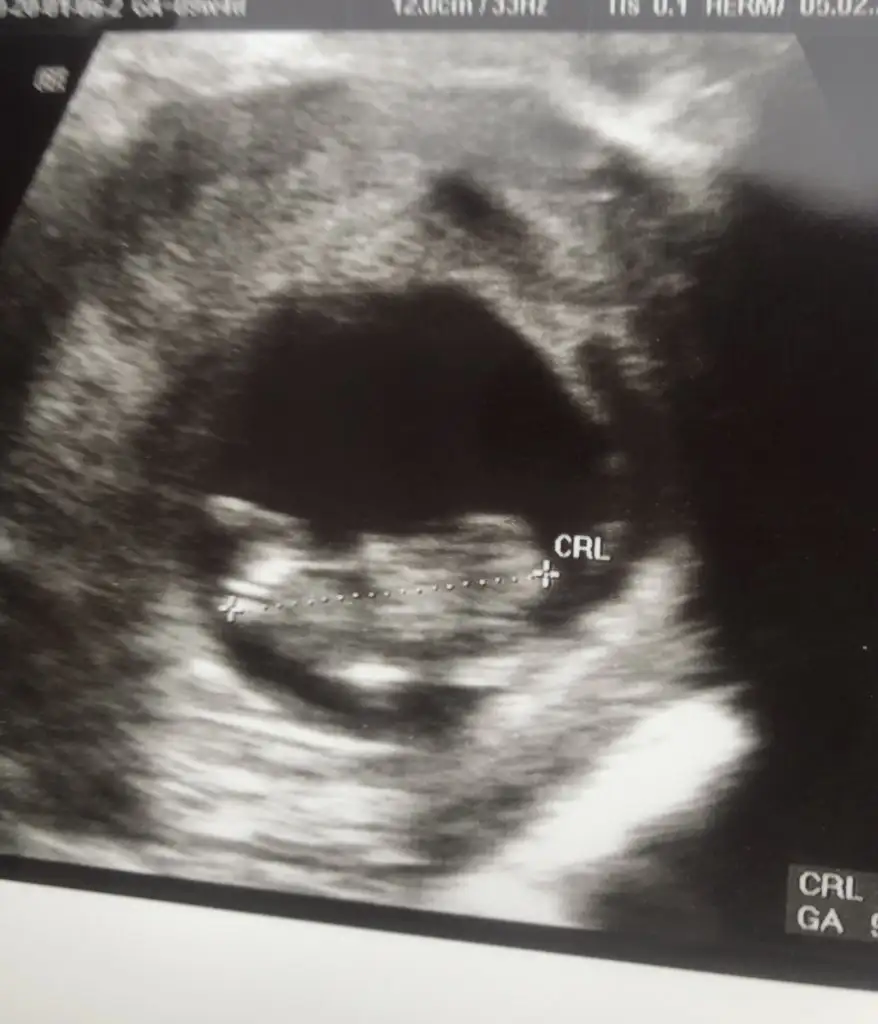

Banada bakarmısınız 12+2 günlükErkek ve kız için 11 yada 12 hafta usg görüntüsü olmalı açıklamalar asagıda yazıyorrabbim herkesin gönlüne göre nasip etsin inşallah .. ecmain

Kız gibi13 haftalık olduk sizce ne olabilir cinsiyeti çok çok merak ediyorum

yine kız yönünde nubuMerhaba. 11. Hafta Usg paylasmistim, kiz olabilir yeniden paylasin demistiniz. Su an 13. Hafta goruntusunu ekliyorum. Tahmin alabilir miyim? Tesekkur ederim. Eki Görüntüle 2593830